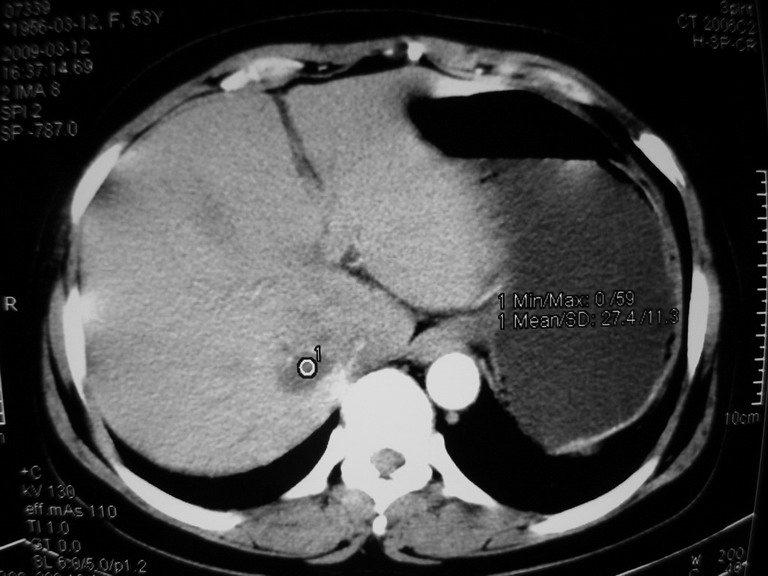

患者,女性50岁,上腹部不适2年余,既往多次腹部彩超未见异常,今日上午在我院查彩超发现肝右叶囊实性病变,外院辅助检查,afp,cea,ca199, 都在正常范围内,无肝炎史否认肿瘤史,生活在牧区

考虑肝癌。缺少延迟片。

考虑炎性假瘤

肝包虫病可能性大